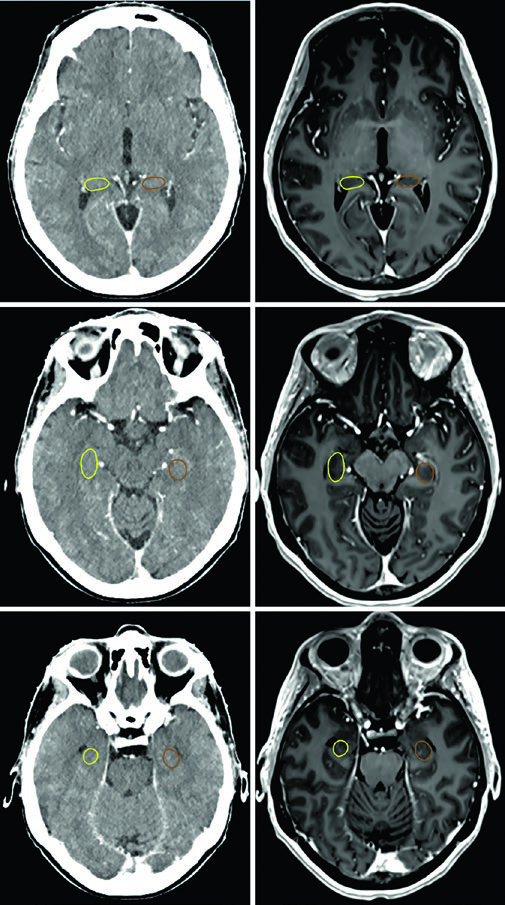

O adenoma secretor de GH da Figura 29.11 demonstra tratamento com SRS a 24 Gy. O tumor toca a margem medial da carótida cavernosa e se estende lateralmente entre as alças da carótida, com envolvimento do seio cavernoso. A dose ao quiasma, nervos ópticos e tronco encefálico permaneceu abaixo de 8 Gy. Na Figura 29.12, o adenoma não secretor mostra invasão do seio cavernoso direito e extensão suprasselar — após ressecção, o tumor residual na sela e no seio cavernoso persistiu.

A Figura 29.13 mostra o planejamento fracionado do mesmo paciente: GTV em coral, CTV com margem de 0,5 cm anatomicamente restrita em teal, PTV com expansão adicional de 0,3 cm. Tronco encefálico, quiasma e nervos ópticos aparecem como OARs delineados. Para macroadenomas, quando a invasão do seio cavernoso é difícil de visualizar, a recomendação é incluir o seio cavernoso inteiro no GTV. Conhecer o tipo de material implantado na sela (músculo, gordura ou retalho de septo nasal) ajuda a diferenciá-lo de tumor residual.